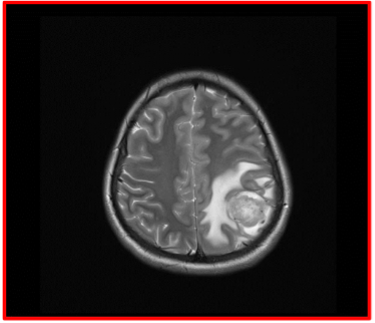

Presentamos un caso Clinico de una paciente con Cáncer de mama y metástasis o diseminación al cerebro y que fue operada realizándose la extirpación del tumor y posterior envío a quimioterapia y radioterapia.

Foto Leopoldo Herrera

Tomografía de cráneo de paciente con Metástasis de cáncer de mama localizado en región parietal izquierda y que se programó para cirugía y retirar el tumor cerebral.